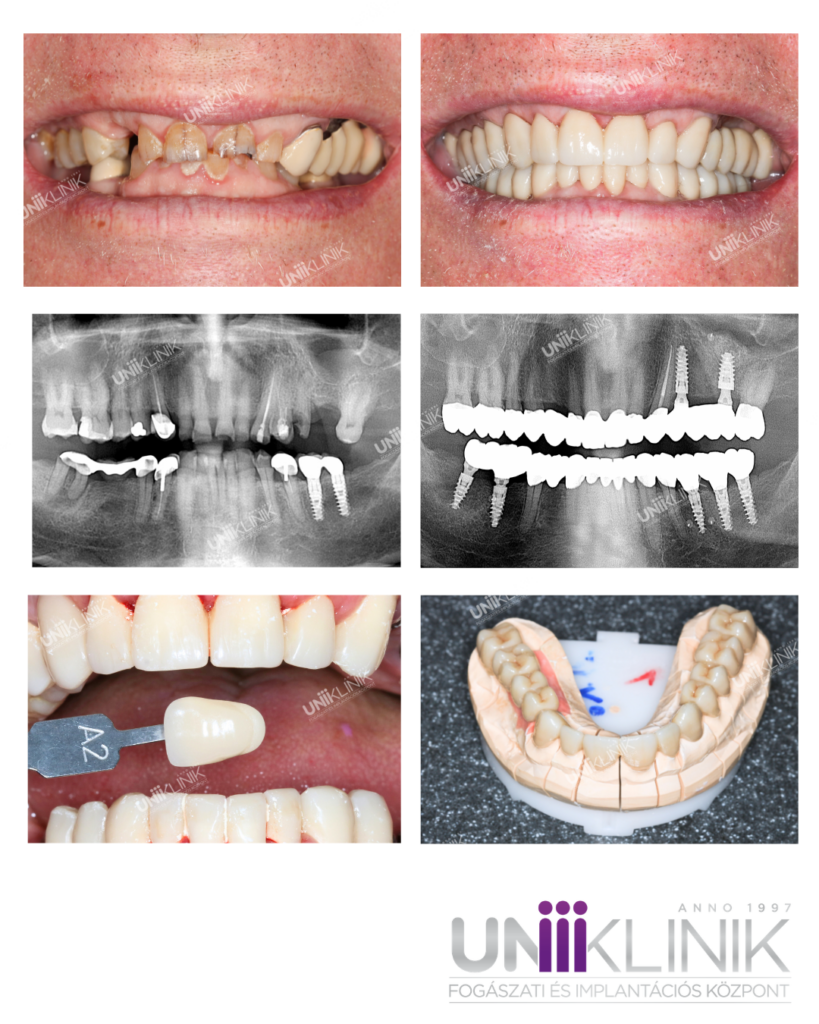

75 éves páciensünk azzal a panasszal keresete fel fogászatunkat, hogy nagyfokú fogkopás következtében állkapocsízületi panaszai alakultak ki és ezért szeretné funkcionálisan és esztétikailag helyrehozni a fogait. Jobb oldali TMJ kattogásról, jobb oldali erős fülzúgásról és rágóizomfájdalmakról panaszkodott.

Dr. Sápi Béla konzerváló fogászat és fogpótlástan szakorvosa fogászatunk gnatológusa (állkapocs ízületi problémákkal foglalkozó ágazat specialistája) első körben Arcus Digma mozgáselemzéssel létrehozott, maximálisan individualizált PMMA, hosszútávú ideiglenes pótlást javasolt páciensünknek az állkapocs ízületi problémák orvoslására.

Dr. Jancsecz Péter fog- és szájbetegségek szakorvosa, dentoalveolaris szájsebész szakorvos páciensünkkel való konzultáció, panoráma röntgen és CT felvétel alapján a foghiányokra Alpha Bio implantátumok behelyezését valamint bal felső állcsontba csontpótlást javasolt.

Maximálisan individualizált PMMA, hosszútávú ideiglenes pótlást páciensünk 6 hónapig hordta. Ez idő alatt TMD panaszai teljesen megszűntek, fülzúgása elmúlt. Közben a foghiányai helyére implantátumok kerültek behelyezésre, a végleges pótlást ezekre, illetve a saját fogaira cirkónium-dioxidból készítettük el. Páciensünk legnagyobb megelégedésére funkcionálisan és esztétikailag is számára tökéletes megoldás született.